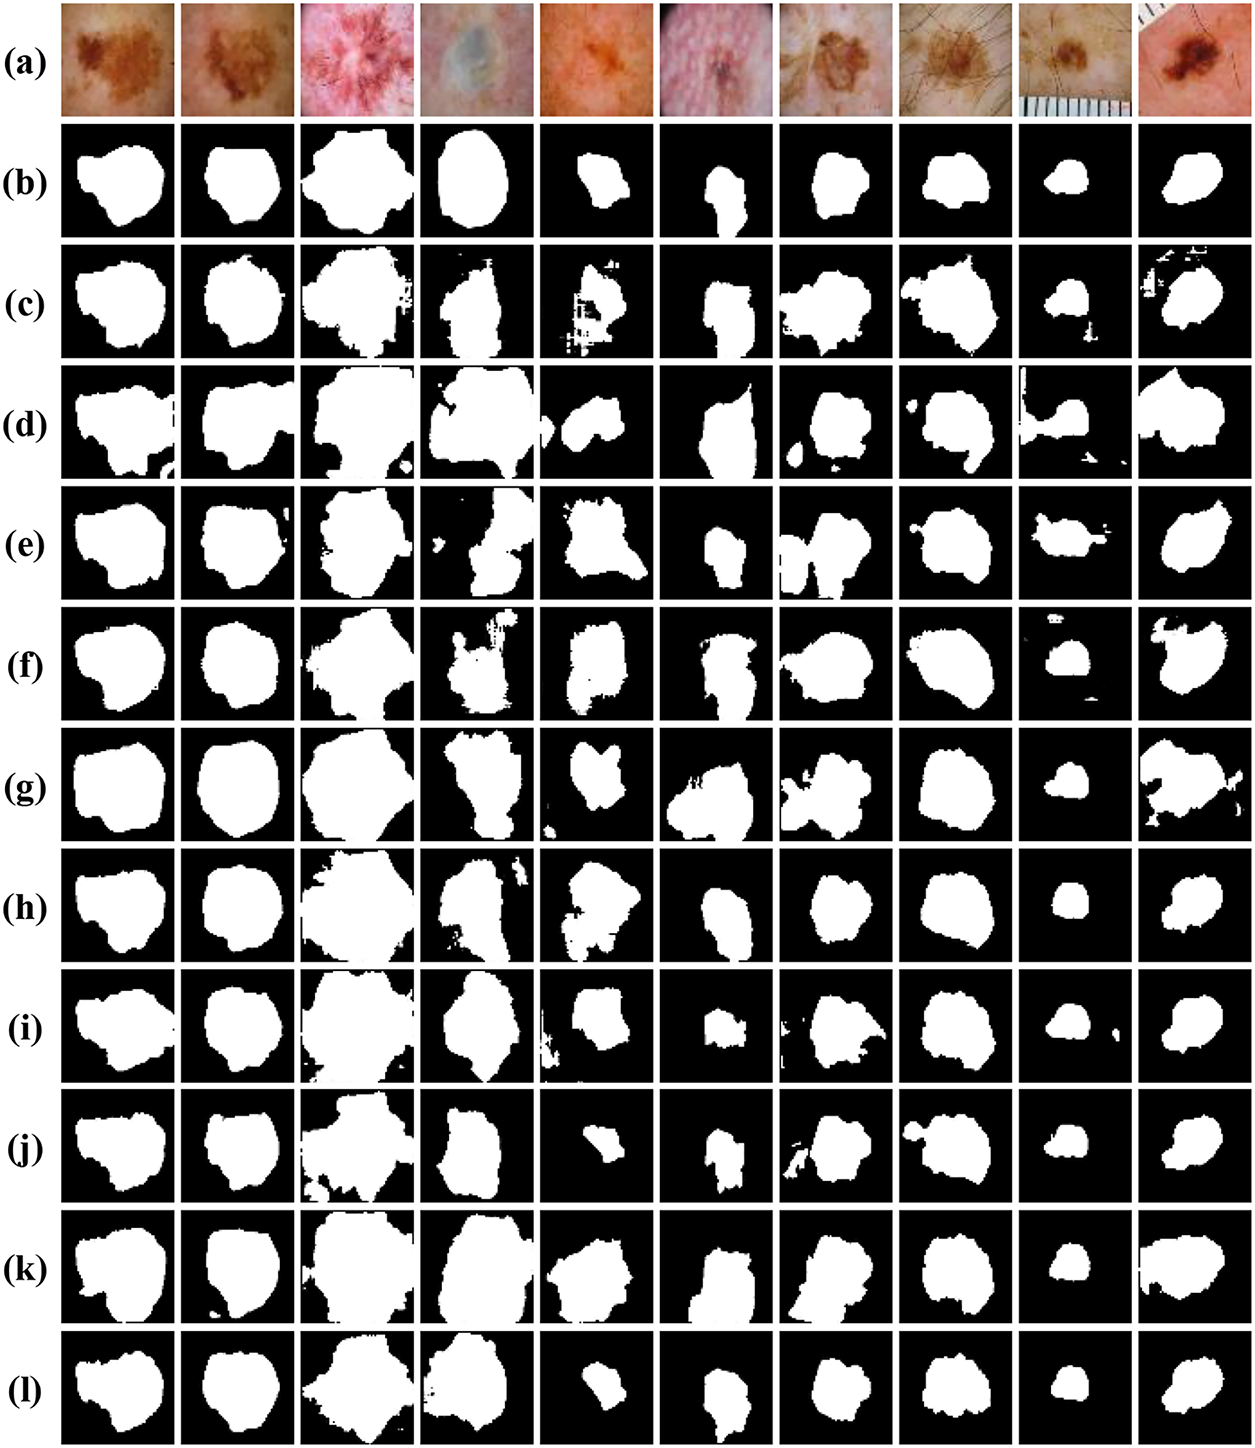

In order to provide a clearer understanding of the segmentation outcomes resulting from the ablation experiments on the ISIC-2018 dataset, a thorough visual comparative analysis was conducted isn this chapter, exemplified in Fig. 9. The segmentation results of the baseline U-Net network are relatively poor, and the location of lesions can only be roughly outlined. With the incorporation of the Dual U-Net architecture, there is a noticeable improvement in the segmentation results compared to the baseline. However, the segmentation still lacks precision. Upon the integration of the MCBAM and SE-Res-Conv blocks into the dual U-Net framework, a notable refinement in segmentation outcomes becomes palpable. Significantly, the segmentation results closely approximate to the gold standard, indicating a substantial augmentation in network performance benefitted from the MCBAM and SE-Res-Conv mechanisms. In addition, with the integration of the MRFB, the segmentation quality is further improved, where the model not only accurately locates the spatial position information of the lesion, but also has a strong ability to recover the boundary and local details.

Figure 9: Visual comparison of ablation experiments on the ISIC-2018 dataset: (a) Original images; (b) Label images; (c) Baseline (Single U-Net); (d) Dual U-Net; (e) Dual U-Net+MCBAM+SE-Res-Conv; (f) Dual U-Net+MCBAM+SE-Res-Conv+MRFB

To comprehensively assess the performance of various encoder-decoder models, we provide visual insights as shown in Fig. 10, showing segmentation outcomes for 10 images from the testing subset of ISIC-2018 dataset. Notably, our method consistently demonstrates superior segmentation accuracy, particularly in scenarios marked by intricate brightness distributions and indistinct boundaries, which present the most formidable challenges. Unlike U-Net, ODsegmentation, CLCI-Net, BCDU-Net, Connected-UNets, MPSU-Net, PMENet, FF-UNet and BiDFDC-Net segmentation networks, which predominantly rely on convolutional techniques, our approach utilizes modules such as the squeeze-and-excitation module, residual connections, MCBAM and MRFB that effectively address limitations associated with extracting global information, especially in instances where the target area is relatively diminutive, or the contrast within the lesion area is notably subdued comparing to normal skin regions. By leveraging these advancements, our method excels in capturing finer segmentation details, as evidenced by the visual results presented herein. This not only demonstrates the robustness of our approach but also highlights its capability to overcome the inherent complexities of dermatological image segmentation tasks.

Figure 10: Visual comparison of different networks on the ISIC-2018 dataset: (a) Original images; (b) Label images; (c) U-Net; (d) ODsegmentation; (e) CLCI-Net; (f) BCDU-Net; (g) Connected-UNets; (h) MPSU-Net; (i) PMENet; (j) FF-UNet; (k) BiDFDC-Net; (l) The proposed method